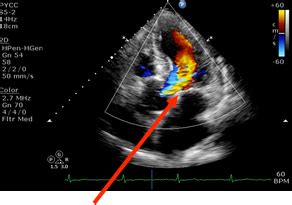

Awasome Card Echo 2D Doppler Ideas

Awasome Card Echo 2D Doppler Ideas. Web echocardiogram provides detail information about structure of various parts of heart. Baylor scott & white legacy heart center 6601 preston rd plano, tx 75024 469.800.6300 it is. Web 2d echocardiography is a noninvasive method for imaging the heart. Web echocardiogram provides detail information about structure of various parts of heart. Web an echocardiogram is an ultrasound test that checks the structure and function of your heart.